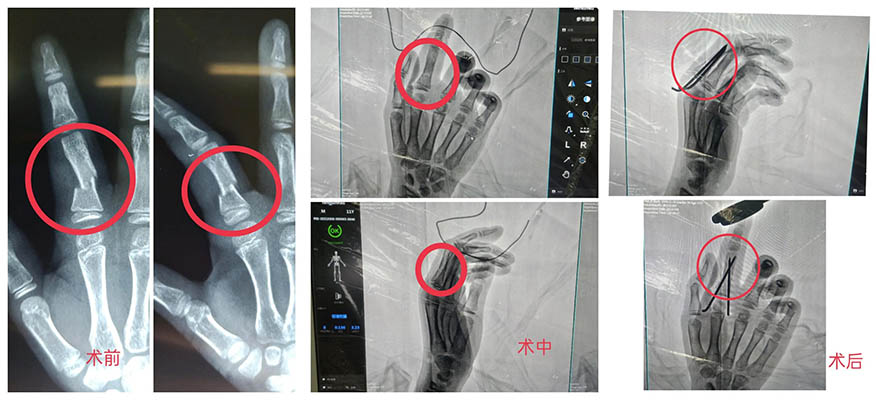

小朋友在家中被歪倒的書架砸傷了右手食指,砸傷后手指腫痛,家長給他噴灑了云南白藥氣霧劑后疼痛仍不能緩解,于是來到我院就診。經拍片檢查發(fā)現,小朋友的右手示指近節(jié)指骨骨折。經過精密的術前準備,創(chuàng)傷外科孫守全主任在麻醉團隊的配合下,為小朋友行右手示指近節(jié)指骨閉合復位克氏針內固定術及石膏外固定術。手術出血少、創(chuàng)傷小,骨折部位成功復位。